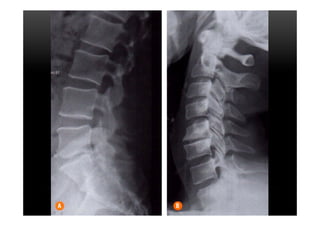

•  Tipo III

•  Alterações caracterizadas por diminuição da intensidade do sinal em T1 e T2 indicando

esclerose reativa que pode, inclusive, ser identificada em radiografias simples.

•  O intenso hipossinal reflete a ausência de tecido medular nas áreas de esclerose óssea

avançada.

•  Apresentação menos frequente que Modic II

MODIC III

PLATÔS VERTEBRAIS •  TipoIII •  Alterações caracterizadas por diminuição da intensidade do sinal em T1 e T2 indicando esclerose reativa que pode, inclusive, ser identificada em radiografias simples. •  O intenso hipossinal reflete a ausência de tecido medular nas áreas de esclerose óssea avançada. •  Apresentação menos frequente que Modic II